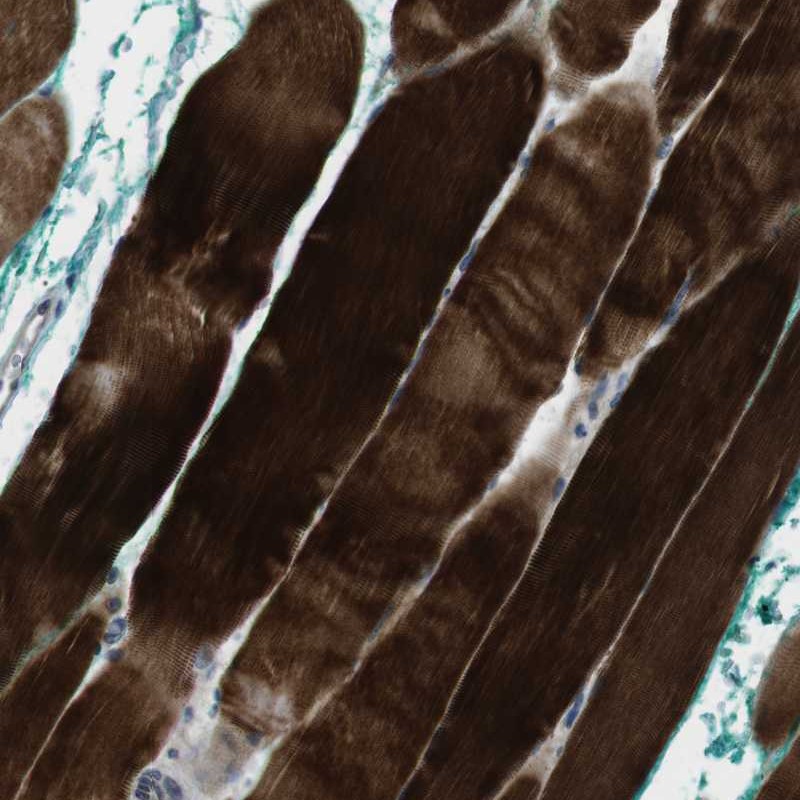

Immunohistochemical staining of human skeletal muscle shows strong cytoplasmic positivity in myocytes.